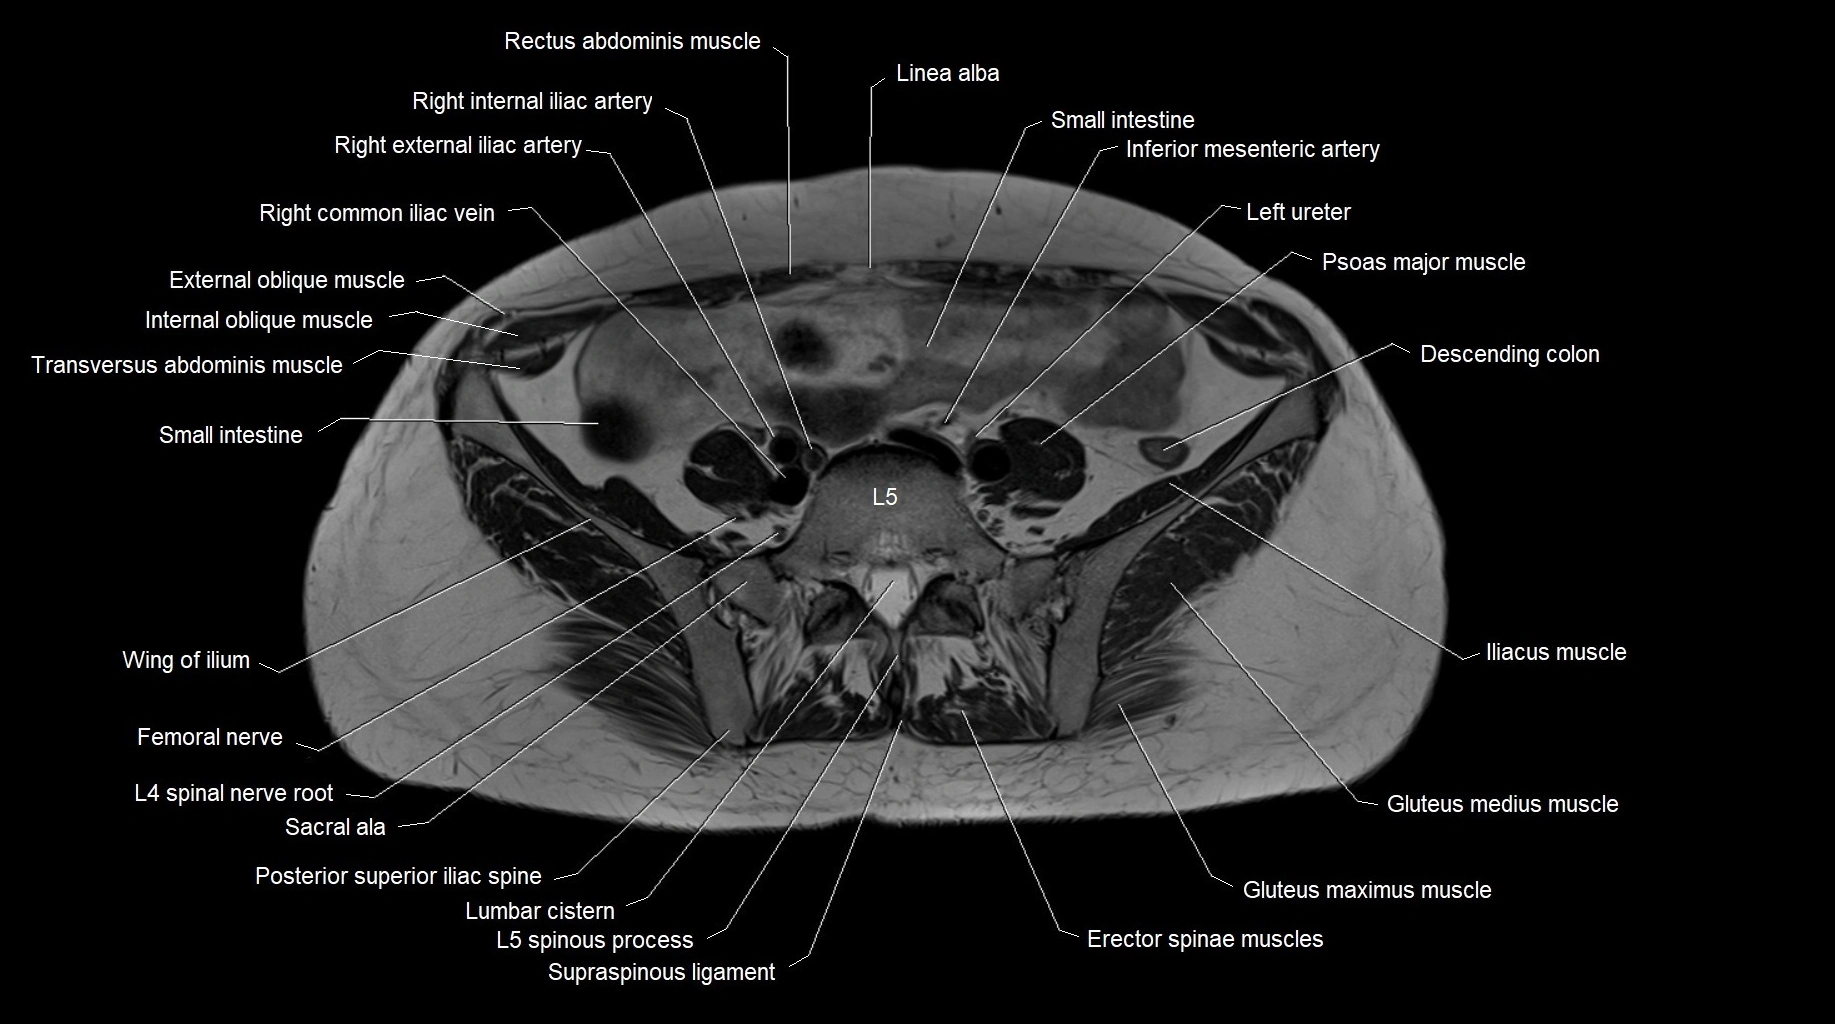

- Psoas major muscle

- Femoral nerve

- Erector spinae muscles

- Ala of ilium (wing of ilium)

- Inferior mesenteric artery (IMA)

- Posterior superior iliac spine

- Sigmoid colon